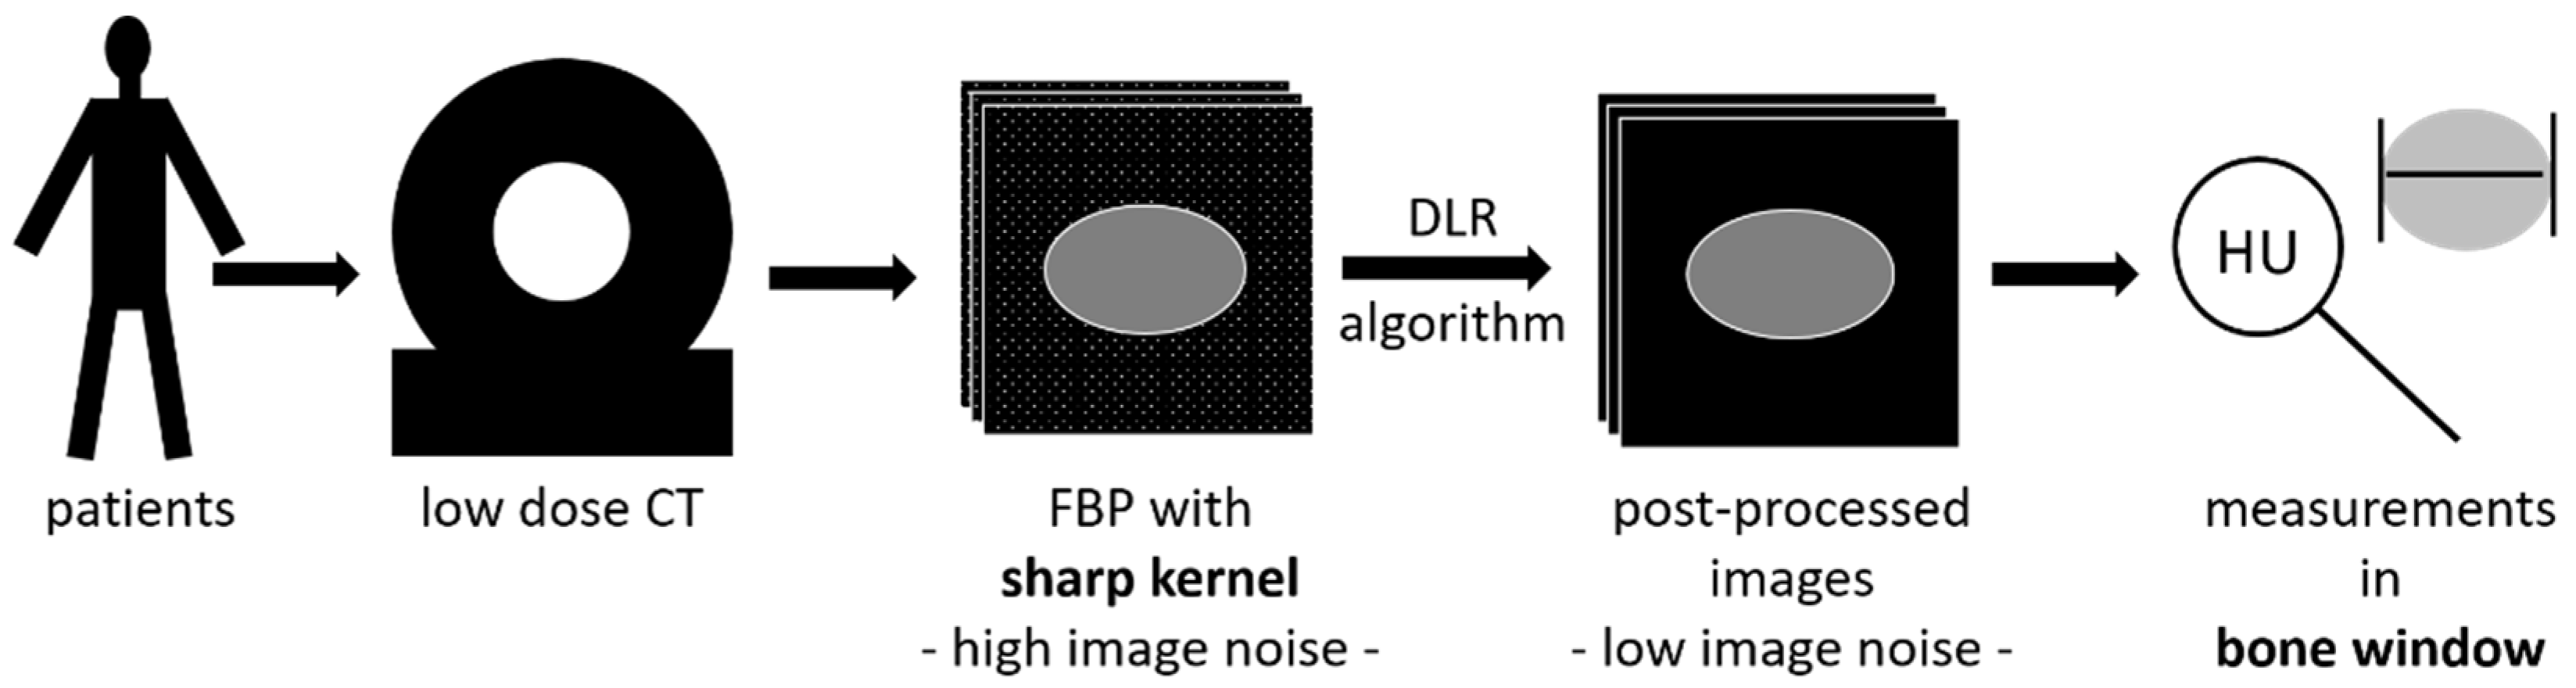

2. Materials and Methods

2.3. Image Reconstruction

- P30f: PixelShine (AlgoMedica), version 1.2.104, using the reconstructed images of (a) with the parameters P214A8S.

- P70f: PixelShine (AlgoMedica), version 1.2.104, using the reconstructed images of (b) with the parameters PB14A4L2.